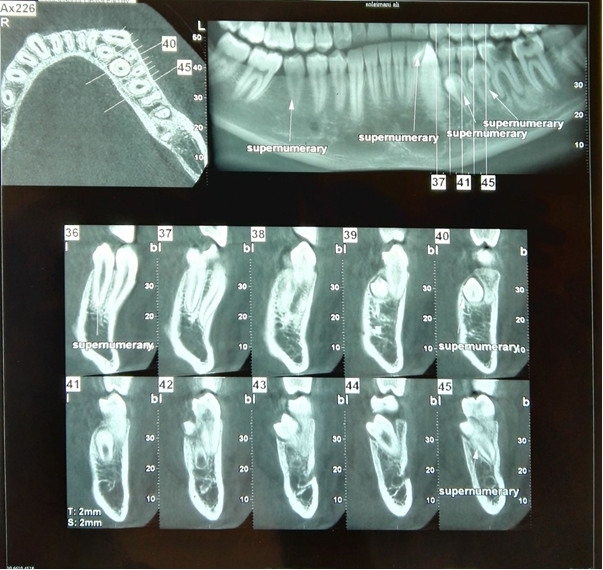

A 19-year-old Iranian male presented for an initial dental examination which involved taking panoramic radiograph. The patient had no complaint of pain, no sign of infection and was in good general health, with no other alterations. The patient has the history of bilateral ulnar polydactyly that was removed operatively at his early childhood. This bilateral ulnar polydactyly was not associated with syndactyly and polydactyly of the feet. On intraoral examination there were no abnormalities in the shape or size of the teeth or the relationship between the patient’s dental and chronological age. And also, there was no any other specific oral finding and relevant familial history of dental abnormalities. On clinical examination no craniofacial and skeletal anomaly related to supernumeraries (e.g. craniosynostosis, absence of clavicles, hypertelorism, ear deformity, etc.) was detected. The panoramic radiograph showed the presence of ten supernumerary teeth in all four quadrants (Fig. 1). On clinical examination it was found that all the permanent teeth including the third molars had erupted and the tooth number 36 had been extracted. CBCT (cone beam computed tomography) of the mandible and maxilla was taken to confirm the location of the supernumerary teeth and impact of these teeth on the adjacent teeth (Fig. 2, 3).

Fig3. Axial, cropped reconstructed panoramic and cross sectional CBCT views of the mandible

The first quadrant showed the presence of three supernumerary teeth. One of them was a distomolar (fourth molar), exhibiting a microdent tooth without complete root formation which lied in the right maxillary tuberosity at the apical region of the 18. A supernumerary premolar had buccally erupted between the 16 and 17. This tooth was normal in size and morphology as a premolar. Another supernumerary premolar was also found palatally to and at about the middle premolar as well. It seems that this supernumerary tooth had resorbed the palatal root of the 14. The gingiva around these teeth appeared healthy, with periodontal probing depths of 2 mm and no bleeding. There were also two supernumerary molars in second quadrant at the level of apical third of the roots of the 28. Both of these exhibit microdontia without complete root formation. These two supernumerary teeth seem to have close proximity with each other. One erupted supernumerary tooth was found in the second quadrant, buccal to and between the 26 and 27. These teeth had fully formed crown and root with normal morphology and size of a premolar. In the left mandibular premolar region there were three supernumerary teeth, all with fully formed crowns and roots. Two of these were unerupted and similar to normal premolars in size and morphology. One of them was between 35 and 36 lingually that resorbed lingual region of the root of 35 and  mesial root of 36 at the middle third of it. The other was between 34 and 35 lingually and resorbed lingual part of the 34 and 35 in their root region too. Another erupted supernumerary tooth which found between 33 and 34 buccally exhibited the normal morphology and size as a canine. One supernumerary tooth was found in the right mandibular quadrant in the premolar region between 45 and 46. This erupted tooth had fully formed crown and root, and  resembled the size and morphology of a normal premolar as well.